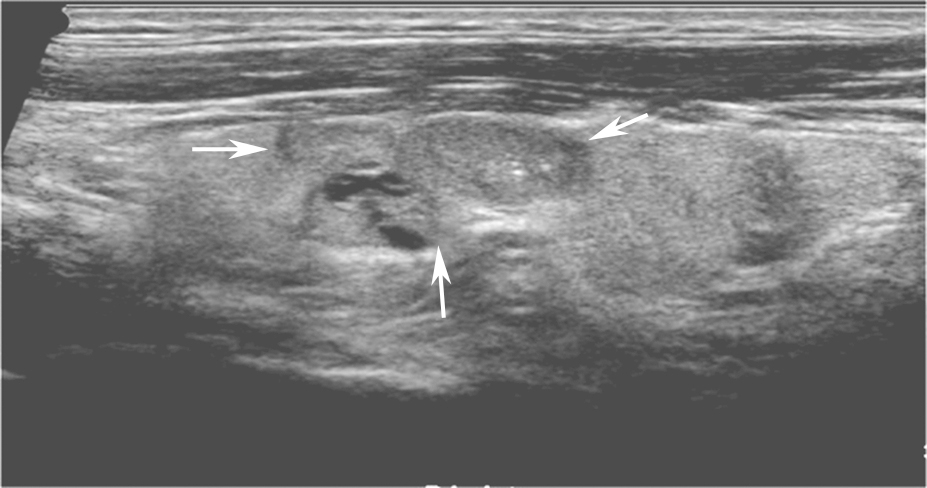

甲状腺髓样癌超声上多为不规则低回声实性结节,内部回声不均,部分病例可伴有囊性成分,髓样癌丰富的血流信号是其超声主要特点。约1/3的髓样癌超声表现不典型,除了血供丰富表现外,类似良性结节(图13、图14)。

图13左侧颈部纵切面:甲状腺左叶中部中低回声(箭头所示),分叶状,可见囊性成分及点状强回声(微小钙化)